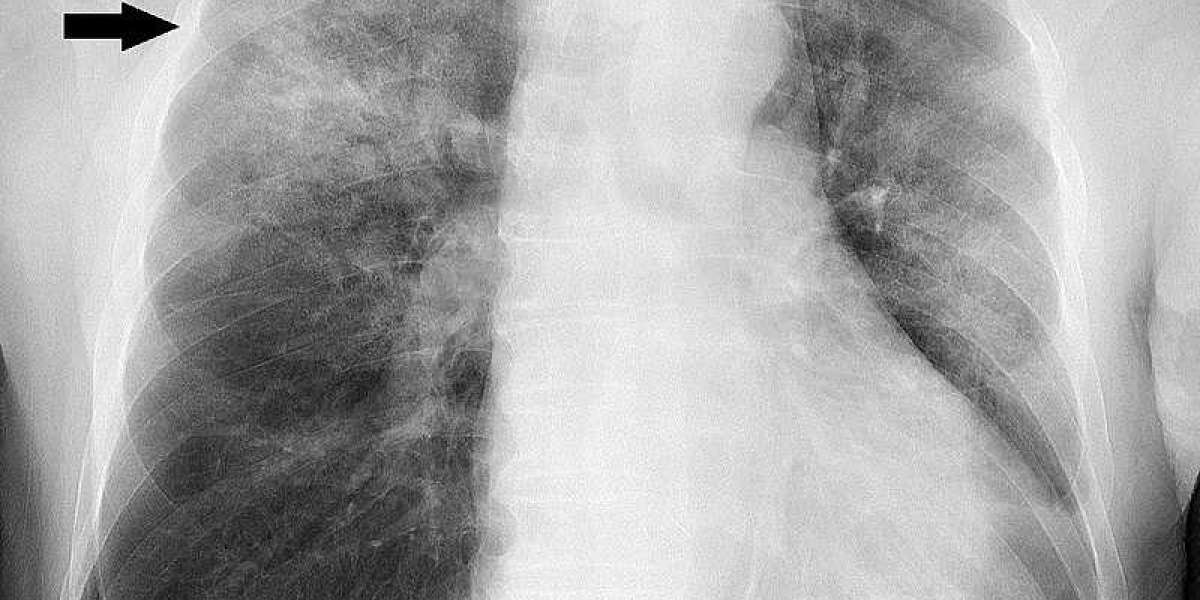

Walking pneumonia, also known as atypical pneumonia or mycoplasma pneumonia, is a milder form of pneumonia that often presents with less severe symptoms compared to traditional pneumonia. Despite its less severe nature, walking pneumonia should not be taken lightly, as it can still cause significant discomfort and complications if left untreated. In this article, we will delve into the symptoms of walking pneumonia, its causes, and the importance of seeking timely medical treatment.

In conclusion, walking pneumonia is a milder form of pneumonia characterized by a gradual onset of symptoms, persistent cough, fatigue, low-grade fever, chest discomfort, and sometimes shortness of breath. It is crucial to recognize these symptoms and seek medical attention for an accurate diagnosis and appropriate treatment. With timely intervention and proper care, walking pneumonia can be effectively managed, allowing for a smooth recovery and a return to optimal health.